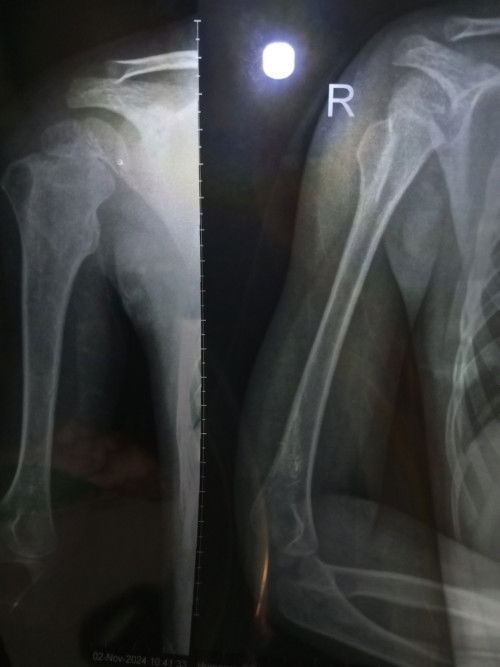

bunda.. ini adalah hasil rontgen anak saya usia 4th7bln. kemaren baru ke dsa aja, dan ini kalau menurut dsa kemungkinan tumor tulang. tp saya harus balik lg lusa, karena harus nunggu hasil pembacanya. kalau memang bener tumor itu harus di operasi. gimana menurut bunda² ya? barangkali disini jg ada dokter ortopedi, bisa tolong jelaskan. saya ga tega liat anak di operasi, baru aja kemaren 3,5th op hernia. dan sekarang harus op lg?? hati rasanya ga karuan bun. #Sharing_dong_Bund #bantujawab #SeriusTanya #ingintahu